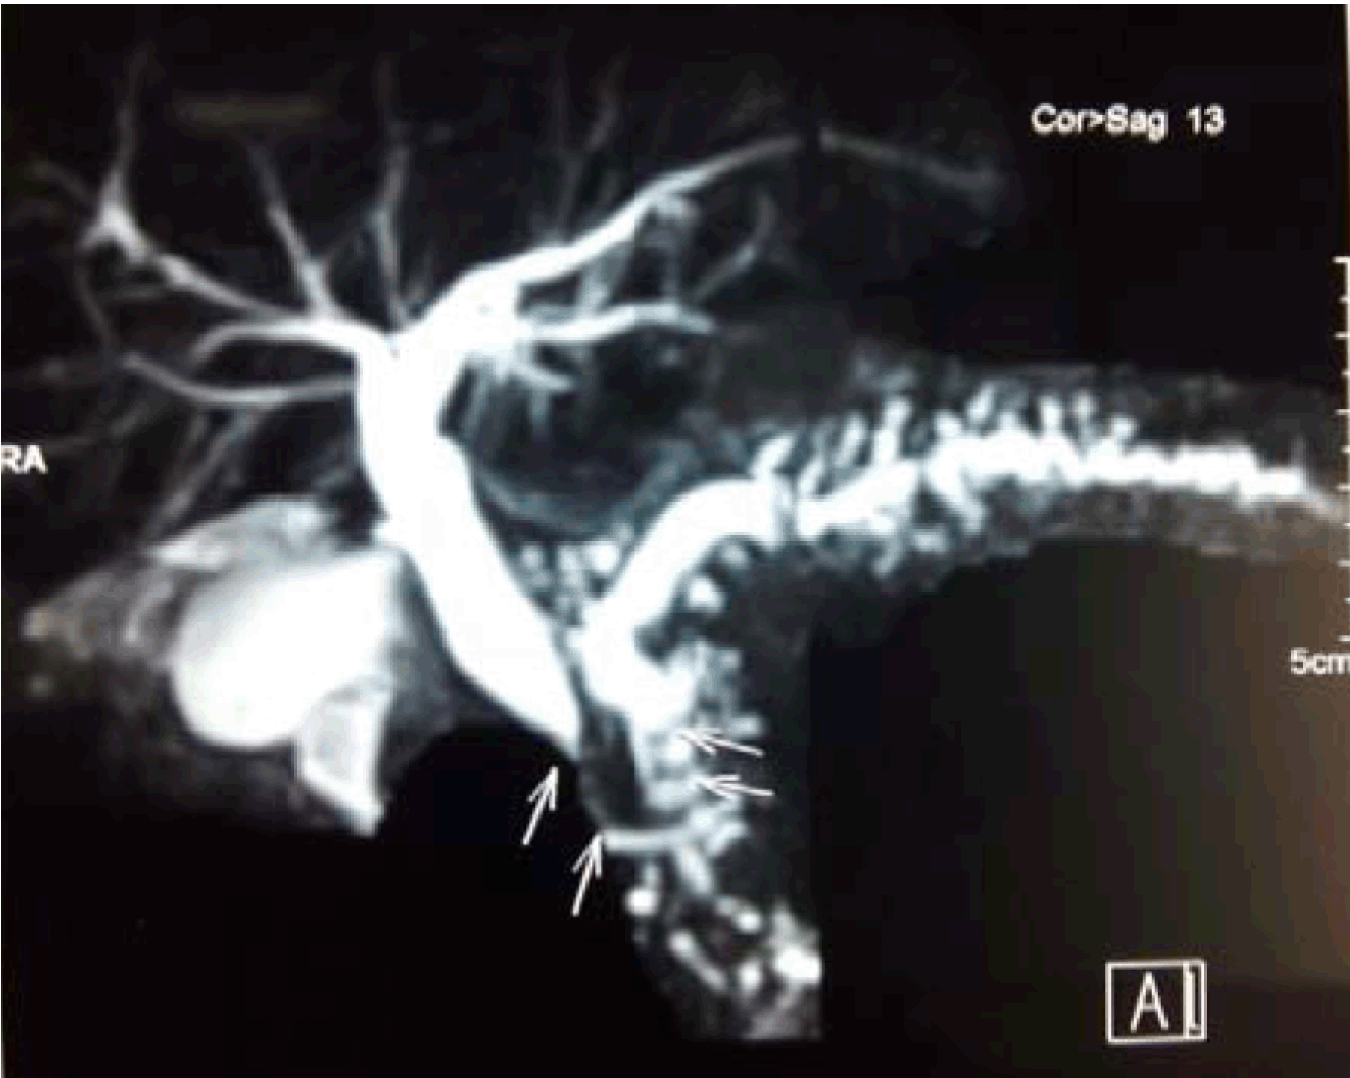

A total of 80 patients were analyzed. Of them 60 were male and 20 were female. The age of the patients varies between 13 to 58 years. The mean age and SD is 37 +10.4 years (Figure 1). Regarding the etiology of chronic calcific pancreatitis, alcohol was associated in 58 patients and 22 patients were considered to be tropical calcific pancreatitis. (Table 1). Of the various complications in this group (Figure 2): Ten presented with diabetes mellitus, six presented with exocrine insufficiency, splenic vein thrombosis with fundal varices was seen in three patients. Pseudocyst in the tail of the pancreas was seen in seven patients. Pancreatic ascites was present in three patients and only two of them without head mass presented with jaundice. All the patients underwent CECT scan to look for calcifications and head mass (Figure 3). MRCP was done in two patients who presented with jaundice (Wadsworth syndrome) both of them had a tapering end of the distal CBD in the absence of head mass (Figure 4). Upper gastrointestinal endoscopy and portal venous Doppler was done for all patients. Only three patients who had splenic vein thrombosis on portal vein Doppler had fundal varices on endoscopy and diagnosed as sinistral portal hypertension. All the patients underwent Frey procedure as already described, amount of tissue cored was measured in grams. Average tissue coring done in the 80 patients is 3.8 grams (Figure 5A-E).

Figure 4: MRCP showing biliary stricture (Wadsworth syndrome).